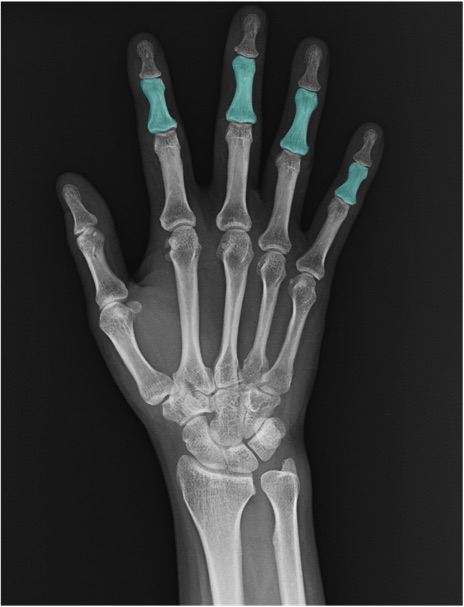

中節骨(middle phalanx)の手関節レントゲン画像における正常解剖

基節骨(proximal phalanx)